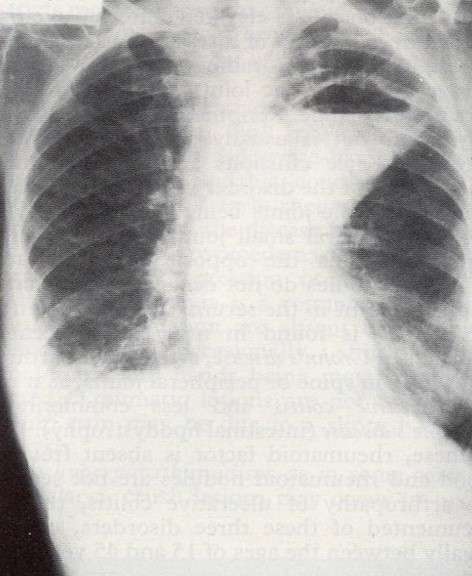

Left upper lobe abscess, right-sided pleural effusion, and left lingular segmental

pneumonia (left image). Edema, erythema, and venous ulceration in the left lower extremity